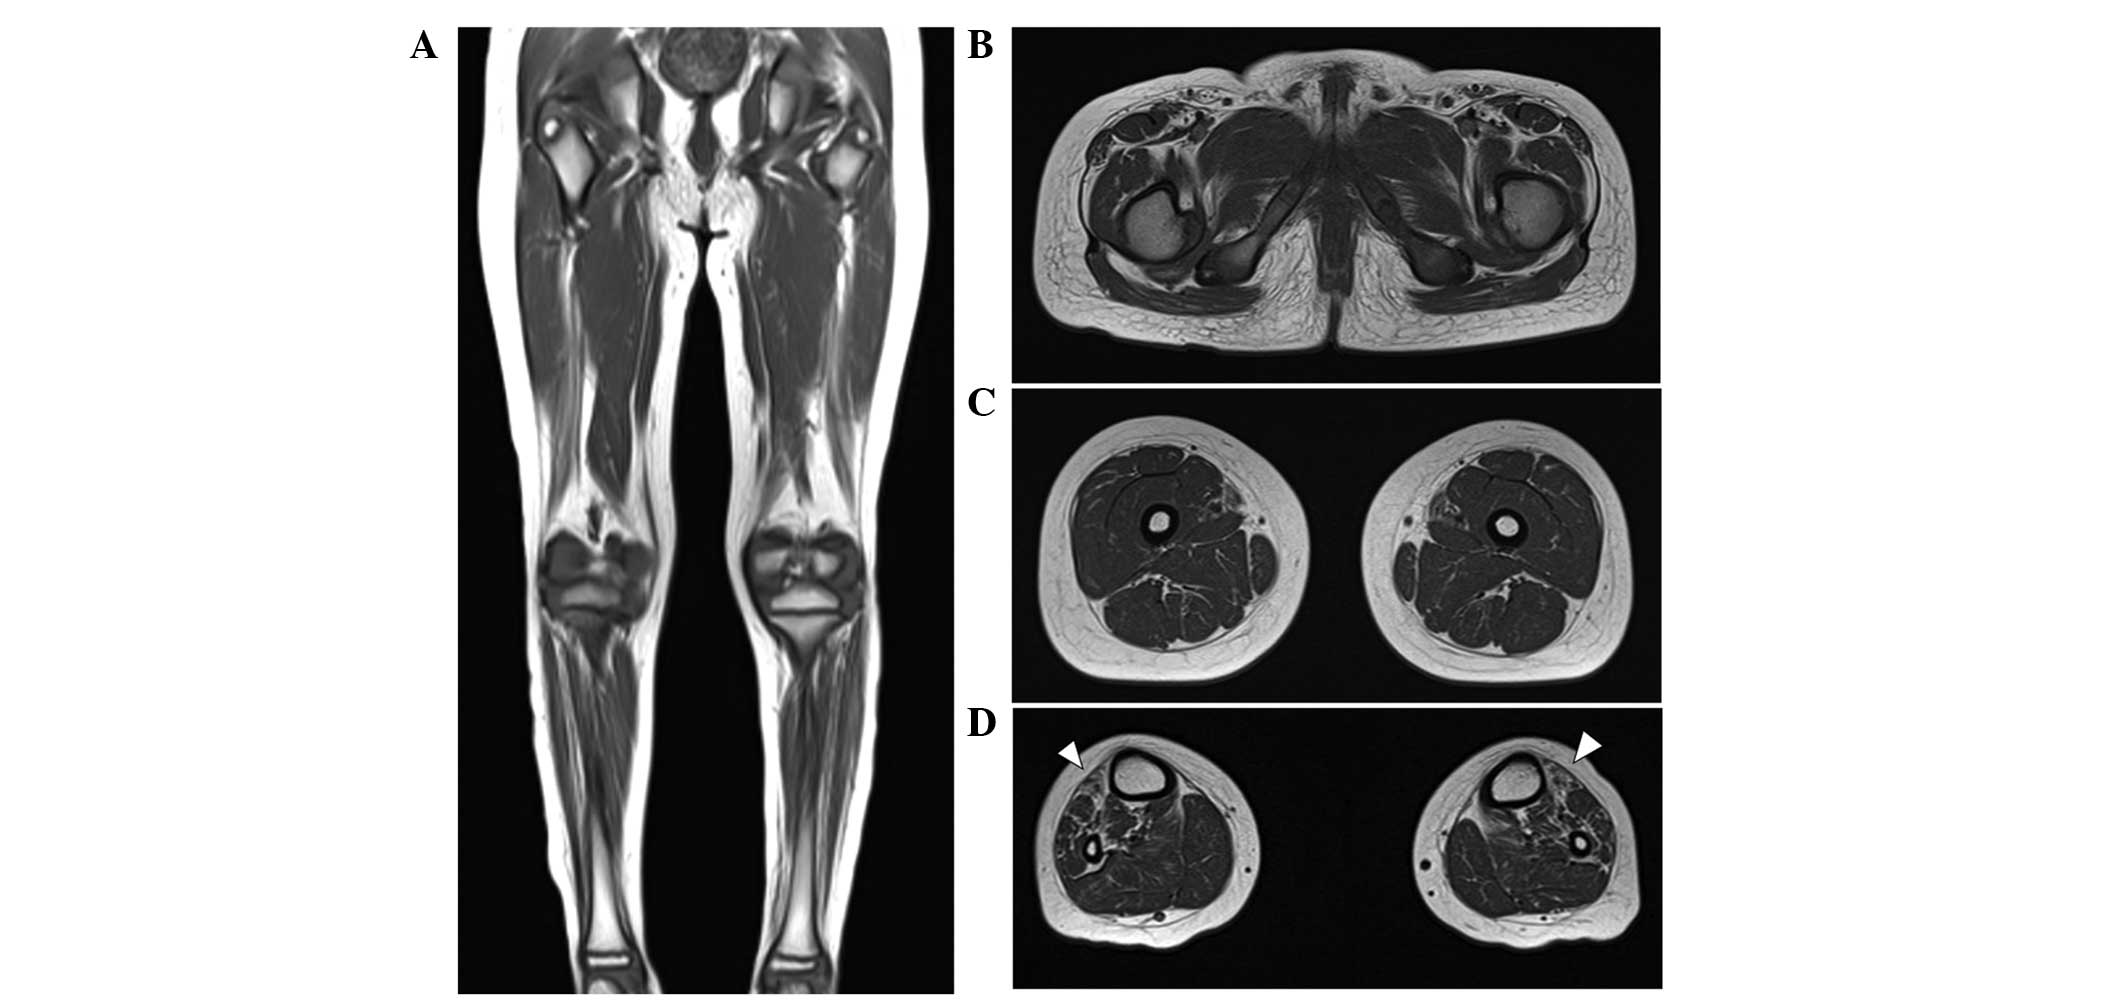

Abstract